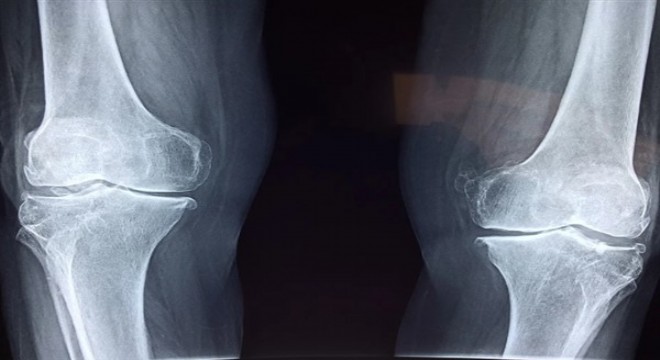

Basit bir kalça filmi erken teşhisi mümkün kılar

Kalça ekleminde hissedilen ağrıda yapılan özel testlerle hastanın belli hareketleri yapıp yapamadığı incelenir. Kalça filmi kalçanın yapısında bozukluk olduğunu gösteren çok önemli ayrıntıları ortaya koyabilir. Böylelikle tedavisi mümkün olmayan, kişiyi protez ile yaşamaya mahkum bırakan bir hastalık olan kireçlenmeye doğru gidebilecek bir tablo, çok önceden tespit edilerek gerekli önlemler alınabilir.